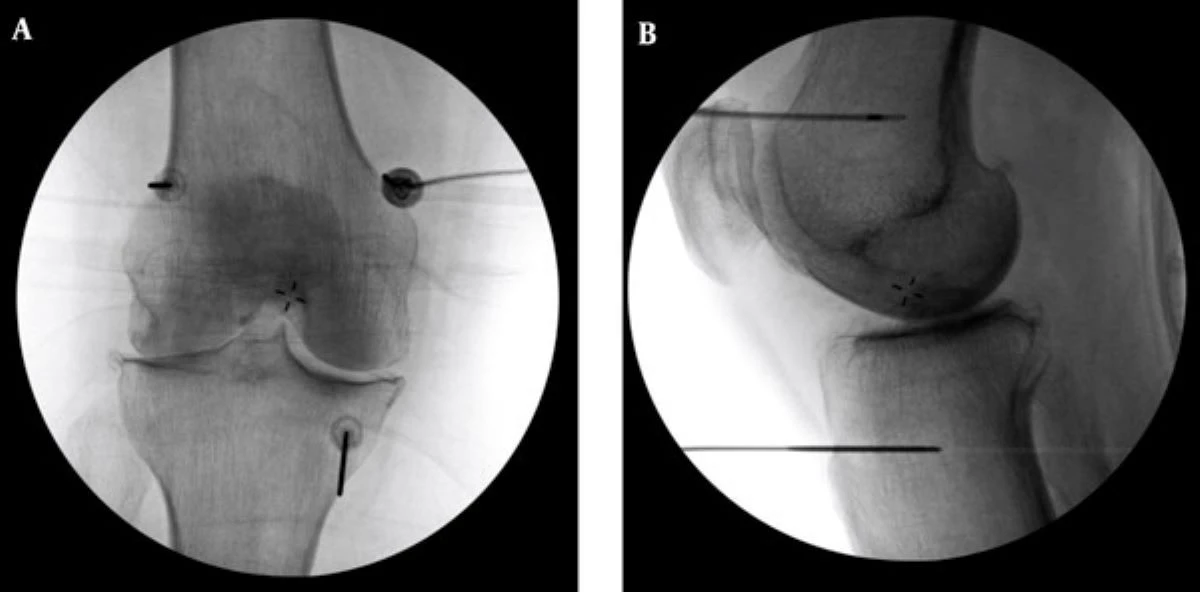

李宜軒解釋,中度以前多能藉由藥物、復健、肌力訓練、生活調整與體重控制改善,至於中晚期則可能需要置換人工關節。針對不適合手術或不願手術的患者,可採用「高頻熱凝療法」止痛,治療在局部麻醉下進行,醫師以X光定位,將電極導針置入膝蓋三處感覺神經叢,並輸出高頻電波,以熱能阻斷疼痛傳導,達到止痛效果。

為確保施行過程中未傷及運動神經,治療前會先進行電量測試並請病人活動膝蓋,確認安全後再施行。多數患者術後當下至一週內即可感受改善,效果約可維持半年~2年不等。若有急性感染、心律調節器或服用抗凝血劑者則不適用,須由醫師評估。